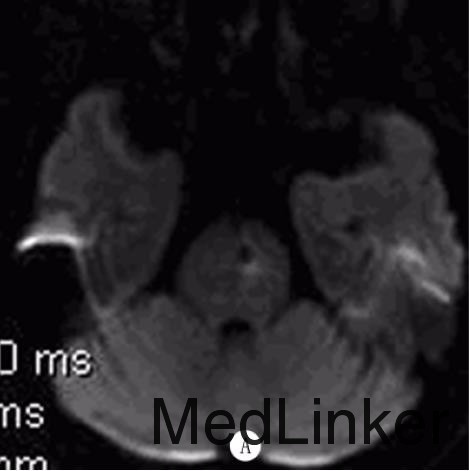

入院查体:BP158/98mmHg,神志清,构音障碍,双瞳孔等大等圆,对光反应灵敏,双眼各向活动充分,未见眼震,示齿口角不偏,伸舌居中,四肢肌张力正常,右下肢肌力4级,余肢体肌力正常,双侧病理征阴性,双侧感觉对称,颈软。急行颅脑CT 检查示:双侧侧脑室周围多发片状低密度影。颅脑MRI检查(距发病30余小时)示:双侧脑实质、脑干多发血管源性脱髓鞘,双侧基底核区多发脑软化灶,DWI序列可见脑桥偏左侧一圆形低密度灶,灶周稍高信号;SWI证实脑桥偏左侧及双侧基底核区多发顺磁性物质沉积。颅脑MRA检查示:颅内动脉粥样硬化改变。颈部血管超声检查示:双侧颈总动脉、左侧颈内动脉粥样硬化斑块(易损斑块)形成。

诊断:脑微出血?给予阿司匹林抗血小板聚集、阿托伐他汀稳定斑块、改善循环及对症支持治疗,病人右下肢无力稍缓解。5d后病人右下肢无力较前加重,查体示右侧肢体肌力3级,复查颅脑MRI示:脑桥偏左侧脑梗死。加用氯吡格雷抗血小板治疗,病人症状渐好转,病情平稳后给予降压治疗,出院时仍言语欠清,右侧肢体无力较前好转。

脑微出血(CMB)反映脑小血管疾病的出血倾向,是高血压性小血管病和脑淀粉样血管病的影像学标志,多被认为是无症状性的,缺乏急性临床表现。但WATANEBE等报道1例在中脑急性形成的CMB导致核上性眼肌麻痹,认为单个CMB在功能区急性形成也可能引发临床表现。此外,脑淀粉样血管病和高血压病人出现短暂性神经功能障碍也可能与CMB有关。该例病人首次出现右下肢无力时颅脑CT及MRI检查均未见明显责任病灶,但DWI序列可见脑桥偏左侧一圆形低密度灶,后经SWI检查证实为CMB。病人既往有高血压史,急性起病,脑内可见多发白质病变、腔隙性梗死等脑小血管病标志,但均非急性形成,在运动传导通路上可解释临床症状的仅有脑桥左侧CMB。由此推测其首次无力原因可能为脑桥单发CMB,此CMB与基底核区CMB影像学表现的不同可能反映了这两类CMB发生机制及病理学表现的差异,其病灶边缘呈环形DWI高信号也支持此CMB为急性形成。提示少数临床疑诊急性脑血管病的病人可能由急性CMB形成引起,对CMB的检测可能有助于诊断和鉴别诊断。但由于该病人发病前未行CMB检测,该单发CMB是否为急性形成尚不能肯定。DOI:10.13361/j.qdyxy.201502039